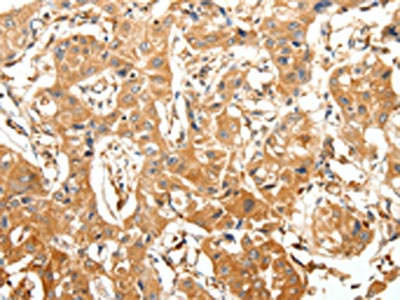

The image on the left is immunohistochemistry of paraffin-embedded Human esophagus cancer tissue using CSB-PA138175(SLC27A1 Antibody) at dilution 1/40, on the right is treated with synthetic peptide. (Original magnification: ×200)

The image on the left is immunohistochemistry of paraffin-embedded Human lung cancer tissue using CSB-PA138175(SLC27A1 Antibody) at dilution 1/40, on the right is treated with synthetic peptide. (Original magnification: ×200)